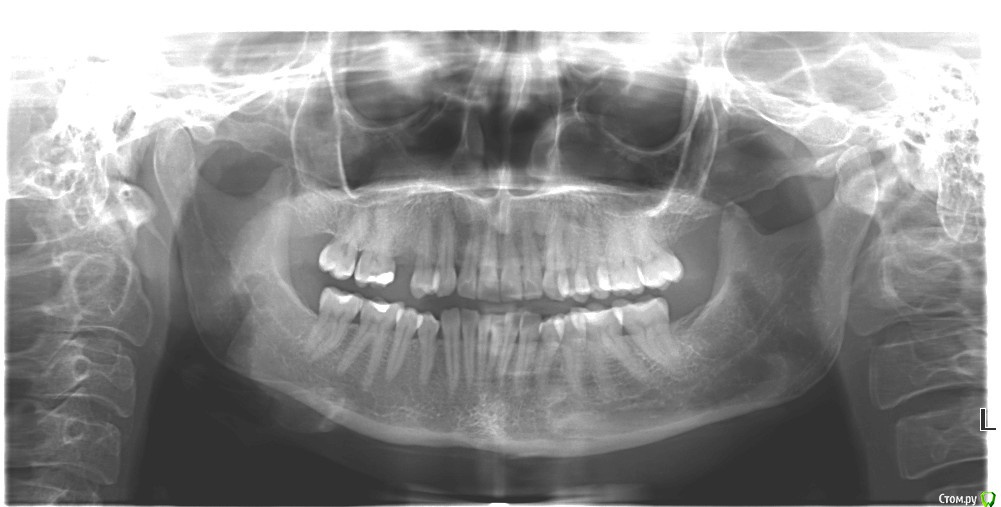

Dashik_ Опубликовано 8 апреля, 2019 Поделиться Опубликовано 8 апреля, 2019 Добрый день, всем присутствующим на форуме! Мне 36 лет. Веду здоровый образ жизни: с детства любовь к спорту, плавание, занятие фридайвингом, йогой, пилатесем. В марте 2017 года откололся 15 зуб, в 2 клиниках сказали удалять, в одной лечить. Не зная, что делать, все-таки решилась на удаление. Удалила зуб 26 мая 2017 года с использованием PRF фракции и PRF мембраны. Так как врач не имел опыта одномоментной установки, отпустил до сентября 2017 года для формирования кости. Через месяц началась ноющая боль на месте удаленного зуба, случился миофасциальный болевой синдром, смещение дисков, гипермобильность сустава. Имплантацию сказали отложить. Сейчас вроде боль ушла, диски вернулись в свое положение, доктор сказал, что можно вставлять имплантат, назначил дату операции. Вставлять собираюсь Астру методом прокола без установки формирователя десны и временной коронки. Коронка планируется через 4 месяца. Типа для внчсников сразу нельзя вставлять с коронкой. Врачу доверяю, но что-то некоторые вопросы не дают покоя.1. Повторный ОПТГ снимок не надо переделывать, предыдущий был сделан 9 июля 2017 года, прикреплен внизу. Годится ли этот снимок ещё для планирования имплантации? Есть ещё КЛКТ от 9.08.2017. Но врач его даже не открывал.2. Доктор не назначил никаких анализов. Кровь можно теперь и не сдавать? На консультации у других врачей, аж ЭКГ назначили и целый лист анализов на кровь.3. Сказал, что вколет в лунку какой-то антибиотик, и возможно, не надо пить антибиотики. Про антибиотик в лунку перед установкой имплантата никакой информации не могу найти в интернете, что это за метод такой? Обычно в попу или таблетки.4. Возможна ли имплантация без приема антибиотиков? Уж больно не хочется пить и колоть антибиотики. Боюсь обострения экземы, была на протяжении 5 лет, сейчас ремиссия в течении нескольких лет. Возобновления дисбактериоза ни к чему. Каковы шансы приживления имплантата без бактериальной терапии? Многие мои знакомые антибиотиков не пили.Всем спасибо за прочтение. Ссылка на комментарий